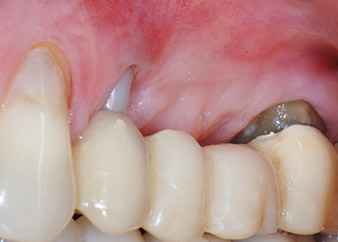

Figures 17 and 18 show the clinical result two months after the surgery. Tooth 24 exhibited reduced mobility of Miller class 1, and the soft tissues were free of inflammation. Probing was avoided at this point of time to prevent reinfection and to avoid violating the epithelial attachment. A control visit was scheduled for reentry and placement of healing abutments, six months after the insertion of the implants.

At the two-months recall, the mobility of the remaining “dental element” 24 was already reduced from Miller 2 to Miller 1. The soft tissue attachment was on the level of the neighbouring tooth 23. Moreover, there were no endodontic or periodontal symptoms, so its prognosis may have to be readjusted.

However, as most of the buccal and proximal bone is missing and the composite build-up extends to the apical section of the root, a higher reattachment level is not to be expected due to biologic reasons (Sculean et al., 2008).